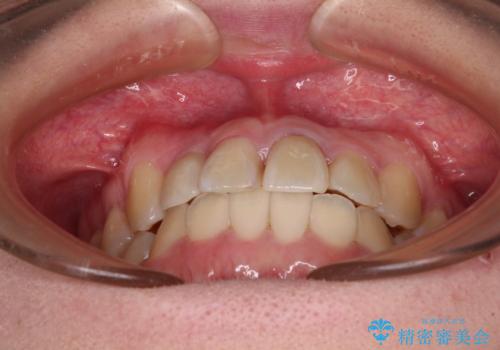

後戻りは軽度であり、インビザラインにて歯列を整え、その後にオールセラミッククラウンにて補綴治療を行うこととしました。

ご家庭やお仕事の都合で通院が途絶えた時期があり、治療は長期間となりましたが、無事に終えることができました。